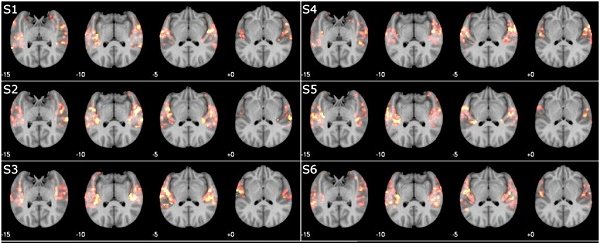

آزمایشات صورت گرفته بر مبنای مدل رمزنگاری-رمزگشایی انجام شد. در این مدل، یک کامپیوتر الگوهای فعالیت مغز حاصل از آهنگهای خاص را زیرنظر دارد و سپس با استفاده از دادههای fMRI تلاش میکند تا آهنگ درست را شناسایی کند.

در این تحقیقات، شش نفر داوطلب شرکت کردند و 40 قطعه موسیقی در ژانرهای موسیقی کلاسیک، راک، پاپ، جاز و غیره برای آنها پخش شد. نرمافزاری که با اسکنر fMRI در ارتباط است بهگونهای آموزش دیده که بتواند فعالیت مغز را در برابر ویژگیهای موسیقایی مانند تونالیته، ریتم و ... ارزیابی کند.

وقتی آنالیز کامل شد، برخی از نواها دوباره پخش شد و سیستم کامپیوتری باید تشخیص میداد که کدام آهنگها انتخاب شدهاند. زمانیکه کامپیوتر از بین گزینههای A یا B باید یکی را انتخاب میکرد، در 85 درصد موارد درست عمل کرده بود.

بعد از آن، وسعت آزمایش بیشتر شد و این بار نوبت نرمافزار بود تا از بین 10 گزینه ممکن، یکی را انتخاب کند. نرمافزار تنها مجاز بهاستفاده از دادههای مربوط به اسکن مغز فردی بود که به آهنگها گوش کرده بود. این بار، کامپیوتر در 74 درصد موارد موفق عمل کرد.